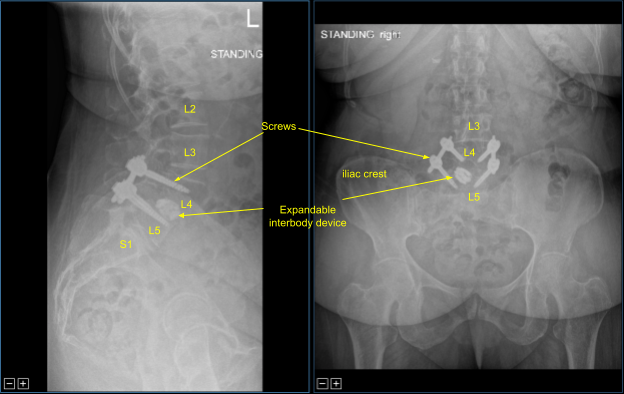

A second intraoperative CT scan was performed showing correct positioning of all of the implanted hardware and instrumentation. Next, calipers were used to determine the length of precut-precontoured titanium rods which were placed across the bilateral L4-5 non segmental pedicle screw instrumentation tulip heads and secured with locking caps.

These were first tightened at L5 bilaterally and then at L4 to achieve reduction of the spondylolisthesis. Approximately 50% reduction was achieved. The locking caps were then final tightened with a torque and anti torque device. The pedicle screw extender tabs were then removed. The wounds were irrigated copiously. Hemostasis was confirmed again.

The patient followed up two weeks after the surgery and then continued following up in our office 4, 6, 8, 12, 24 weeks with sequential X rays. In their last office visit the patient stated they were able to do their usual activities and that physical therapy was going well.